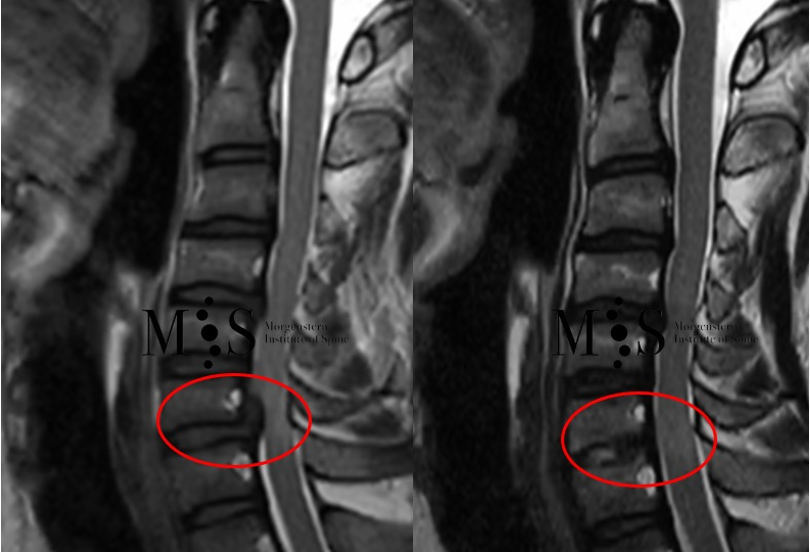

Imagen izquierda: Imagen de RMN de una compresión de la médula cervical en nivel C6/C7 (marcada con el círculo rojo) con signos de mielopatía. Imagen derecha: imagen de control de RMN del mismo paciente 2 meses después de la cirugía en la que se observa la completa descompresión y liberación de la médula espinal.

Paciente de 48 años con una compresión de la médula espinal cervical en nivel C6/C7 y mielopatía del cordón medular en ese nivel. Se realizó descompresión por cirugía endoscópica anterior por una incisión de 9 mm de longitud. A las pocas horas de la cirugía el paciente se movía libremente y alta hospitalaria pocas horas después.